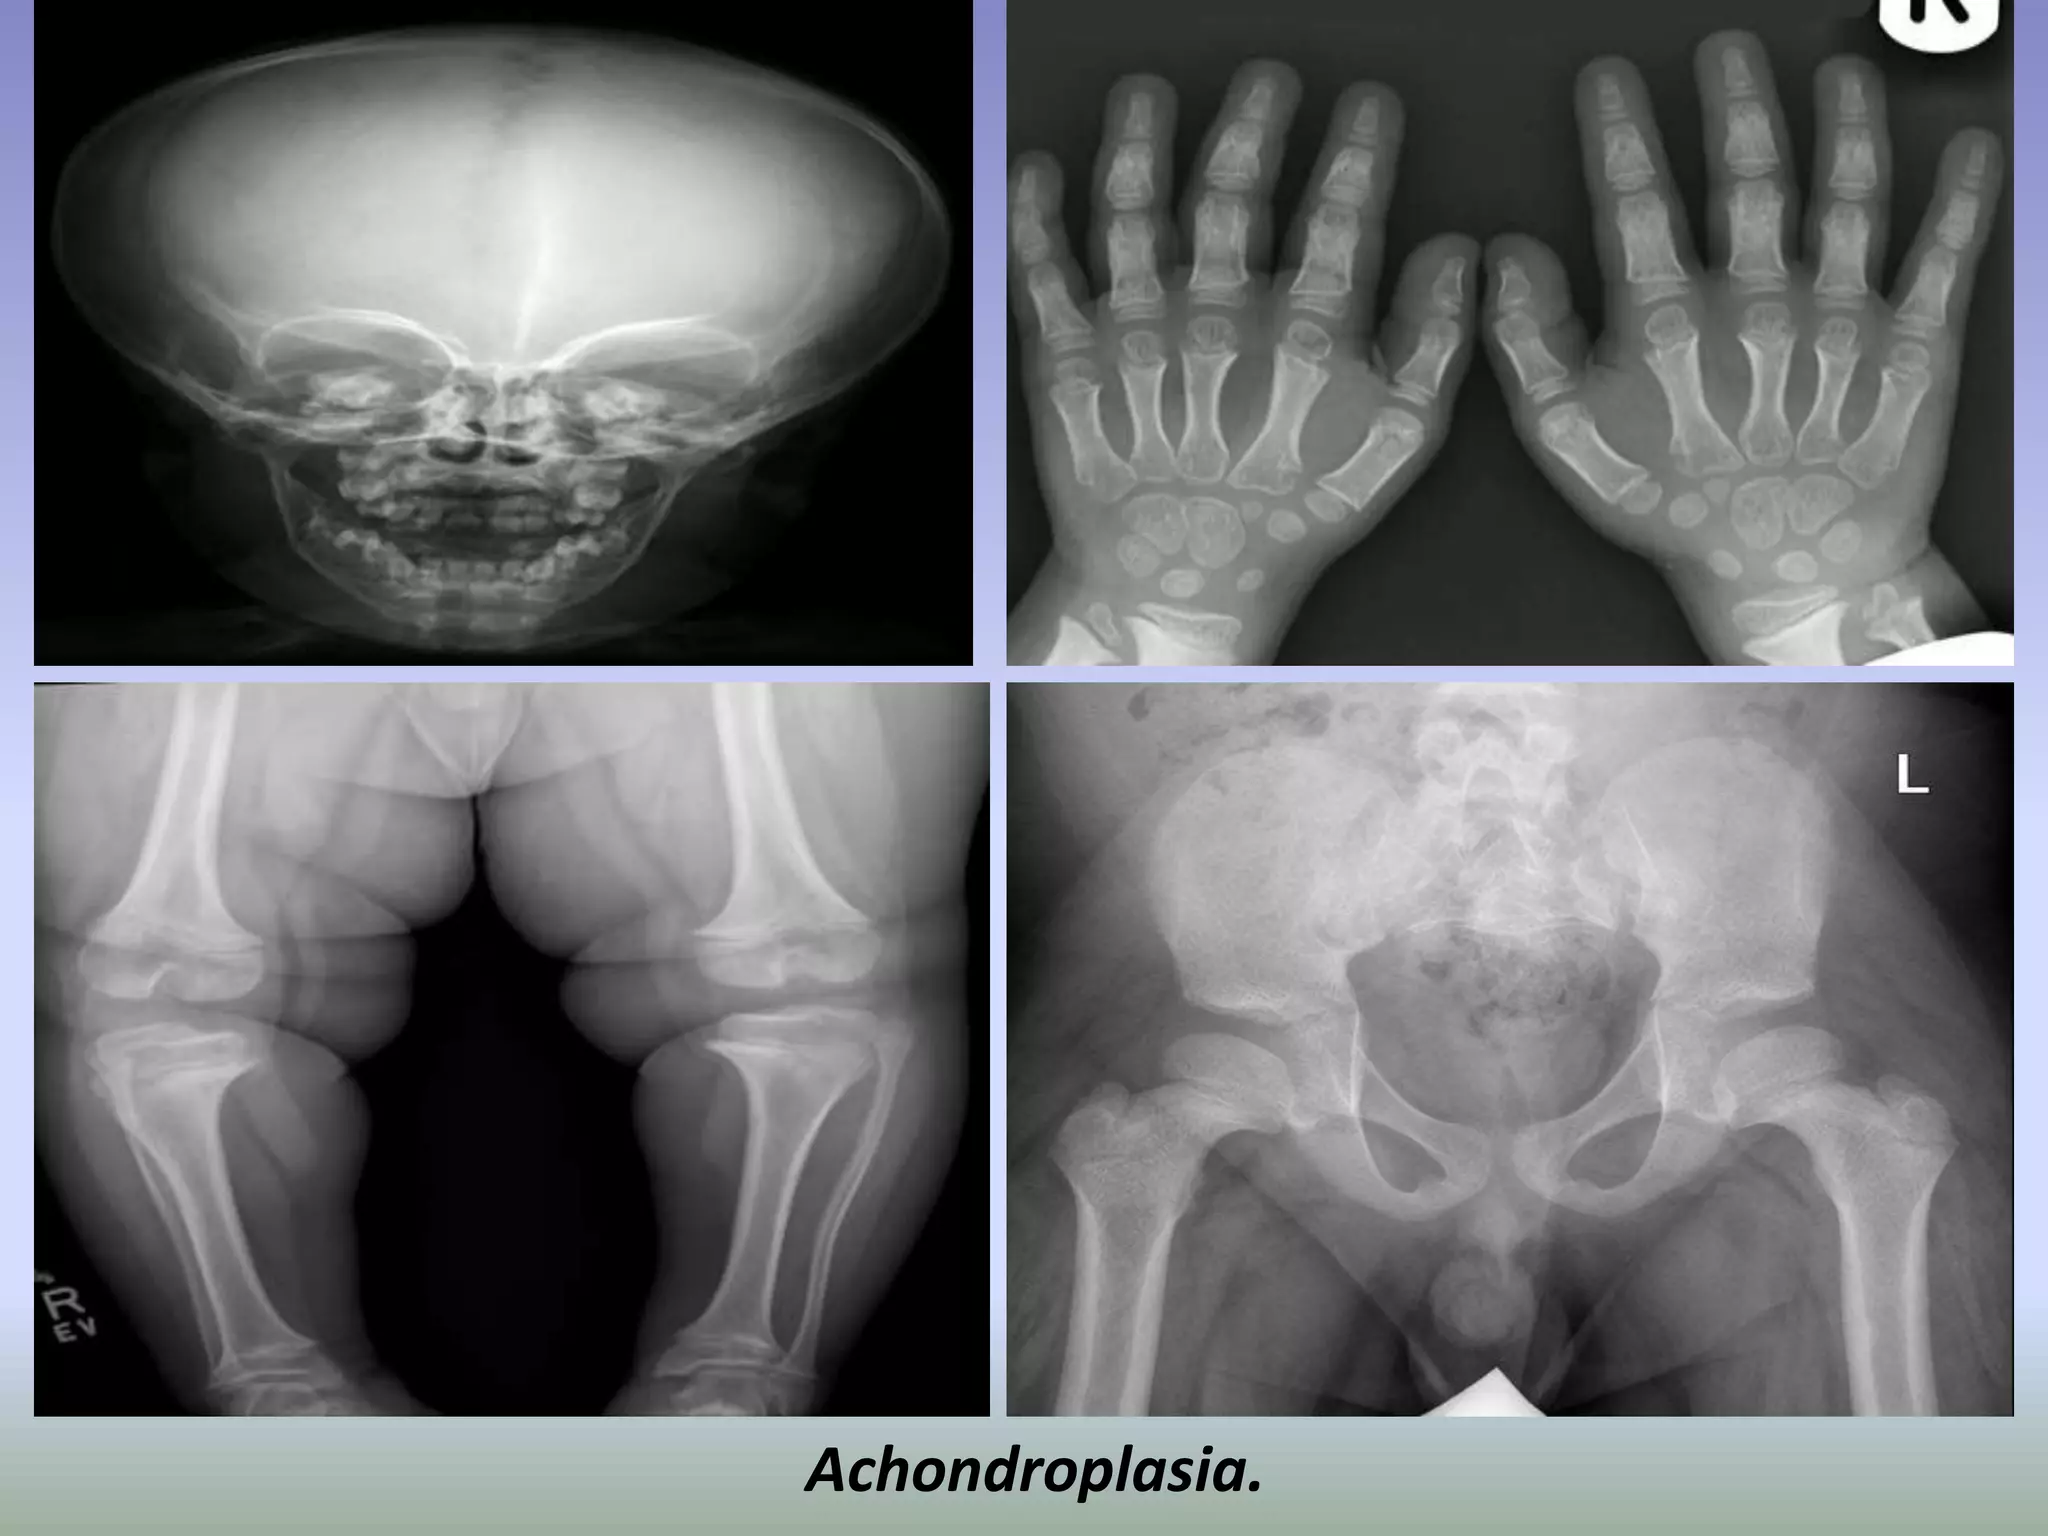

Achondroplasia.